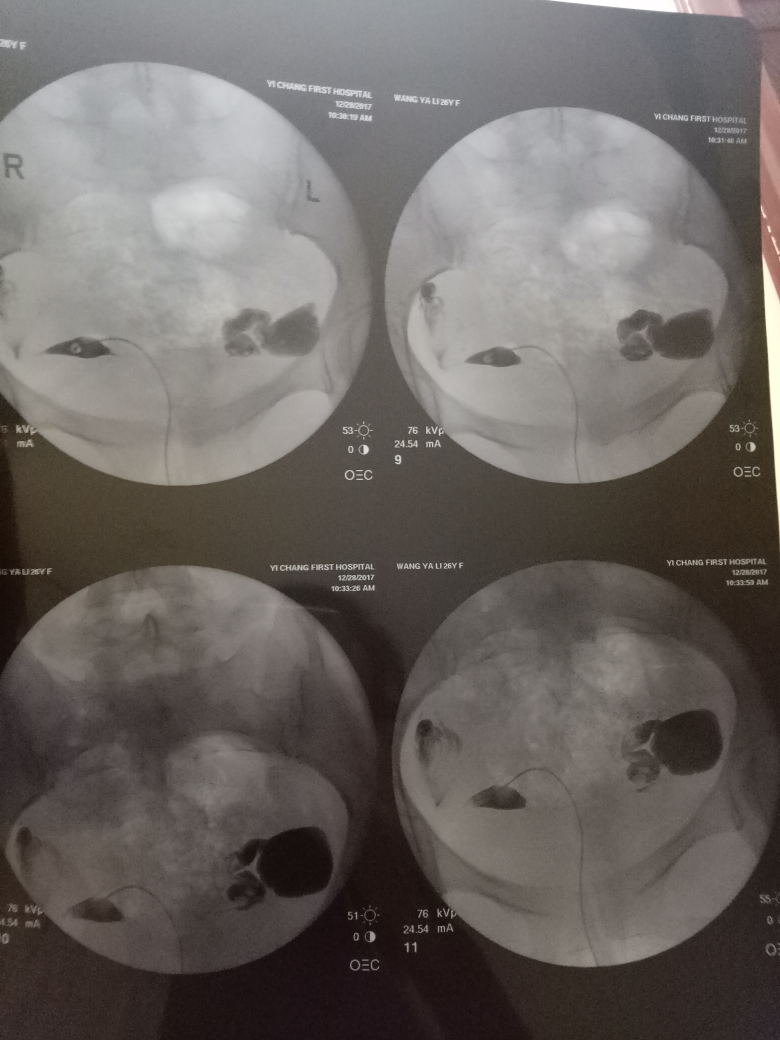

在現(xiàn)代醫(yī)學(xué)中,造影技術(shù)廣泛應(yīng)用于臨床診斷,對(duì)于不孕癥的診斷和治療也起到了重要作用,造影是一種通過(guò)放射線、超聲波等影像技術(shù)觀察人體內(nèi)部結(jié)構(gòu)和狀況的方法,完成造影后的第二個(gè)月,很多夫婦關(guān)心是否容易懷孕,造影本身并不會(huì)直接影響懷孕,但了解身體情況后,有針對(duì)性地進(jìn)行治療和調(diào)理,確實(shí)有助于提高懷孕的幾率。

通過(guò)造影技術(shù),醫(yī)生可以清晰地觀察到子宮內(nèi)部環(huán)境,如子宮內(nèi)膜厚度、輸卵管通暢情況等,若子宮環(huán)境良好,第二個(gè)月懷孕的機(jī)會(huì)將大大增加。

造影技術(shù)還可以評(píng)估卵巢功能,如卵泡數(shù)量、質(zhì)量等,若卵巢功能正常,有助于排卵和激素分泌,從而提高懷孕幾率。